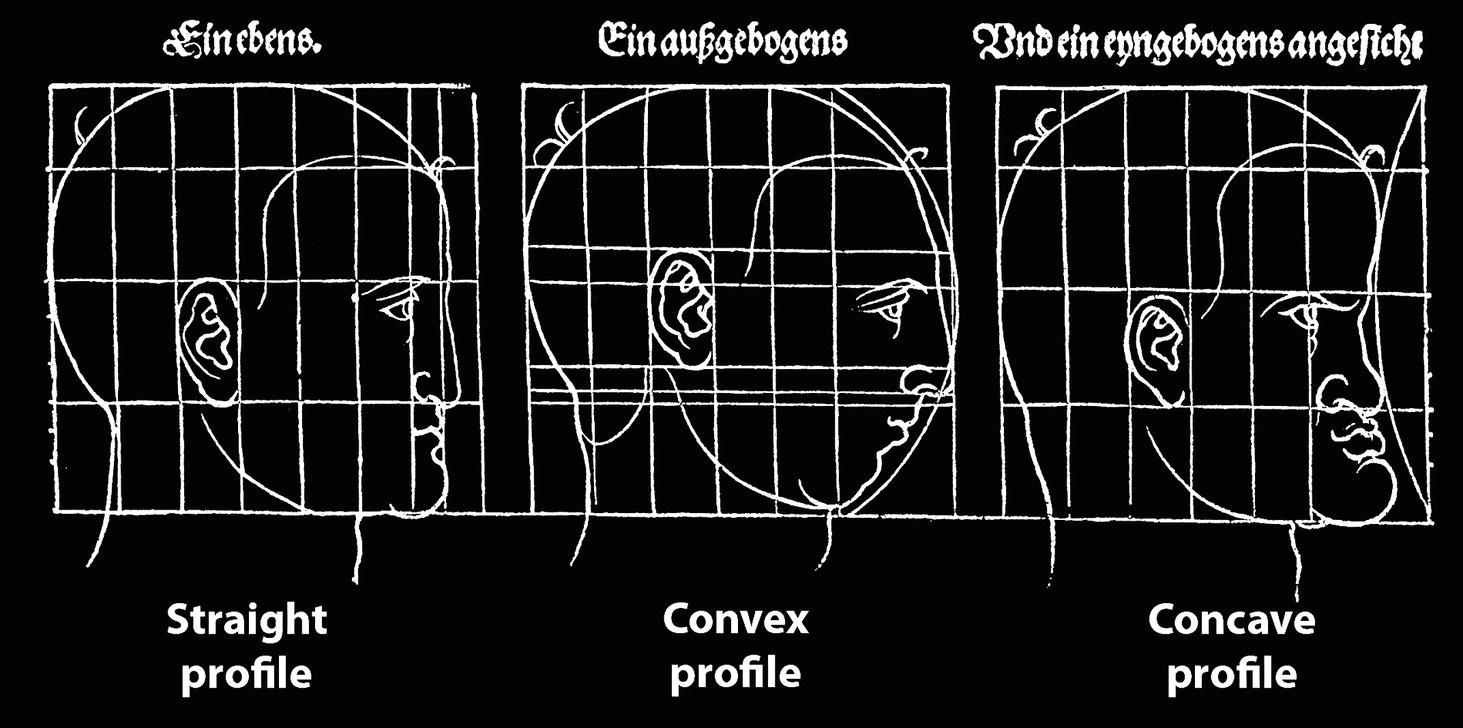

‘It is the common wonder of all men, how among so many millions of faces, there should be none alike’. Sir Thomas Browne (1605–82), English physician and writer, Religio Medici (1643)1 Individual variability is a fundamental principle in human biology. One of the most variable and distinguishable parts of the human body is the craniofacial complex. Clinicians will often compare a patient’s craniofacial measurements and proportions to the so‐called population norms (normative values) or even to classical ideals. However, Simon (1926) stated: ‘all we ever find are variations; an exact, ideal normal does not exist, cannot exist. And this is our enigma; in theory we will never find the normal, in practice we forever feel its need and apply it constantly’.2 The use of population norms may be logically enhanced by evaluating normal ranges of variability. Therefore, clinicians must have a thorough understanding of the normal ranges of variability in every aspect of craniofacial form, depending on age, sex and ethnic variability. Developmental disorders, as well as traumatic injuries and pathological conditions, may lead to deformities of the head and the face. Therefore, clinicians need to have a thorough understanding of the normal anatomy and morphological range of variation of the craniofacial complex in both males and females of different ages and ethnic groups, to act as guidelines when treatment planning the restoration of normal craniofacial proportions. Classifications that are useful for descriptive purposes include: A proportion index provides a numerical expression of the proportionality of a region of the craniofacial complex. The use of proportion indices dates back through the history of craniometry, particularly in the late nineteenth century. Linear (chord) or surface (arc) distances of the skull were measured between a variety of defined craniofacial landmarks; with any two measurements, the smaller was expressed as a percentage of the larger in order to provide a proportion index value. These could be used to provide an indication of skull shape. Figure 8.1 Determination of the normality or abnormality of any craniofacial measurement (or proportion index value) obtained from patients may be evaluated by comparison with the normative values obtained from a normal (average representative) population sample. The normal range of measurements is provided by the mean ±2 standard deviations (SD). The shape of the normal distribution curve shown is determined by the population standard deviation. Craniofacial parameters with small SDs have narrow, taller curves and those with large SDs have broader, flatter curves. Approximately 68% of all values fall within the range of ±1 SD from the mean and 95% within the range of ±2 SD from the mean. The normal range of variability for any craniofacial parameter is taken as being equal to the mean ±2 SDs. Greater differences may be perceived as deformities of gradually increasing severity. The leading researcher in the field of craniofacial anthropometry from the mid‐1960s to the early 2000s was Leslie Farkas, from the University of Toronto. Farkas et al. collected a large quantity of highly relevant anthropometric data between 1968 and 1984, from 2564 individuals.3 These data were used to provide 166 individual facial ratios, presented as proportion indices. In the creation of an index, the smaller measurement is multiplied by 100 (numerator) and divided by the larger measurement (denominator). Thus, a proportion index involves two linear craniofacial anthropometric measurements, with the smaller being expressed as a percentage of the larger. Proportion indices permit objective, quantitative assessment of facial morphology and proportions. Farkas3 identified two basic categories of proportion indices: Each proportion index will have a mean index value and a range of variation for a given population group, based on age, sex and ethnicity. The standard deviation (SD) determines the normal (average) range of variability of an index, from 2 SD below to 2 SD above the mean. Index values within this normal range are regarded as variations of normal proportions.4 Measurements within ±1 SD of the mean are regarded as optimal. The relationship between two measurements is disproportionate if the proportion index value is outside the normal range (Figure 8.1).4 For a number of facial parameters, single morphological measurements or proportion index values may have a large SD and, therefore, wide normal ranges of variation; as such, only measurements or proportion index values which differ considerably from the mean of the population will be perceived as deformities. Conversely, other facial parameters may have very small normal ranges of variability, in which case even a small difference from the mean may be perceived as a deformity. The cephalic index (index cephalicus) is a numerical expression of the ratio between the head width (biparietal diameter) and head length (fronto‐occipital diameter) of a living person. The cephalic index (CI) is calculated by the formula (Figure 8.2): Figure 8.2 Cephalic index. Where: The cephalic index is used in anthropometry to classify head types as (Table 8.1; Figure 8.3): Table 8.1 Classification of anatomical head types Index values according to Martin and Saller.5 Figure 8.3 Head types. The highest cephalic index values occur in the Chinese and the lowest values in African Americans. The larger index values of the Chinese differ significantly from those of whites or blacks (Table 8.2).6 A comparison of the cephalic index values of three ethnic groups was undertaken; North American Caucasians, northern European (German) and eastern European (Czech). The index values indicated a mesocephalic head type for both sexes of North American Caucasians and northern Europeans; and a brachycephalic (short‐wide) head type for the eastern Europeans.6 The head circumference is measured in the horizontal plane around the head, through the glabella and opisthocranion. However, it may be measured across ophyron (the point ‘On’, in the mid‐sagittal plane, of a line tangent to the upper limits of the eyebrows) rather than glabella in order to eliminate the effect of development of the frontal sinuses and superior orbital rims on head circumference.5,7 African Americans have the largest and the Chinese have the smallest head circumference for both sexes. The head circumference is slightly larger for blacks than for whites for both sexes.6 The initial step in facial analysis involves the examination of the face in frontal view in order to assess the overall facial shape. The variety of facial shapes is almost limitless. However, a simple assessment will allow an overall categorization of the basic facial shape. The basic facial shape in frontal view may be any combination of the following: Table 8.2 Cephalic index of three ethnic groups Data modified from Farkas.6 SD = standard deviation. Table 8.3 Head circumference of three ethnic groups Data modified from Farkas.6 SD, standard deviation. Figure 8.4 Facial height‐to‐width ratios. Variations in facial height and width result in an innumerable variety of the three basic facial shapes (round, square and triangular). For example, an oval facial type is a combination of an overall round face combined with increased vertical facial height and/or reduced facial width. The relationship of vertical facial height to facial width is an important indicator of overall facial shape. There are three methods of evaluating the vertical facial height‐to‐width proportion. These may be presented as proportions, percentages or indices: The facial index (index facialis or index of the morphological face height) is a numerical expression of the ratio between the facial height (nasion to menton) and the bizygomatic facial width (zygion to zygion) of a living person. The facial index (FI) is calculated by the formula: Where: The facial index is used in anthropometry to classify faces as (Table 8.4; Figure 8.6): Figure 8.5 Facial types according to Albrecht Dürer. (Modified from Dürer, 15288.) Figure 8.6 Facial types. Table 8.4 Classification of anatomical face types Index values: male according to Garson, 1885;9 and female according to Martin and Saller, 1957.5 The term facial divergence was introduced by the orthodontist‐anthropologist Milo Hellman,10 although the concept had been described by Albrecht Dürer (1528) (Figure 8.7).8 It is essentially a description of the slope or inclination of the face in the sagittal plane (Figure 8.8). It is determined by the sagittal position of soft tissue pogonion (Pog’) and subnasale (Sn) relative to a vertical line dropped from glabella (G’), with the subject’s head in natural head position. The factor that discriminates and distinguishes facial divergence from profile convexity or concavity is the sagittal position of subnasale (Sn) relative to the G’‐Pog’ line. In order for the face to diverge anteriorly or posteriorly, yet not to exhibit signs of convexity or concavity, subnasale (Sn) must be on or nearly on the G’‐Pog’ line; i.e. the upper facial plane (UFP, G′‐Sn) and the lower facial plane (LFP, Sn‐Pog’) are in a straight line, but diverge anteriorly or posteriorly. Figure 8.7 Facial divergence according to Albrecht Dürer. (Modified from Dürer, 15288.) Figure 8.8 Facial divergence. Anthropometric data from North American Caucasian males and females with untreated Class I dental occlusions describing normal facial divergence and ranges of variability has been provided.11 Mean values of facial divergence are negative, with the faces being slightly posteriorly divergent. Anterior divergence does not occur until two standard deviations from the mean. Facial divergence is essentially an ethnic variation in facial profile form. With a straight profile, i.e. no excessive profile convexity or concavity, anterior or posterior facial divergence is compatible with a normal maxillo‐mandibular and dental occlusal relationship. Figure 8.9 Facial profile contour according to Albrecht Dürer. (Modified from Dürer, 15288.) Figure 8.10 Facial profile contours. The contour of the facial profile may be described as convex, straight or concave. This concept was described by Albrecht Dürer (1528) (Figure 8.9).8 With the patient in NHP, the overall contour of the facial profile may be described by the relationship between two lines: the upper facial plane (UFP), connecting glabella (G’) to subnasale (Sn), and the lower facial plane (LFP), connecting subnasale to soft tissue pogonion (Pog’). In a straight profile, these two lines form a nearly straight line. Such a facial profile is termed orthognathic (Greek orthos: correct or straight; gnathos: jaw). An angle between these two lines indicates facial profile convexity (pogonion behind relative to subnasale in the sagittal plane), or facial profile concavity (pogonion ahead relative to subnasale in the sagittal plane). A convex profile indicates a skeletal Class II jaw relationship (and/or sagittal chin deficiency), and a concave profile indicates a skeletal Class III jaw relationship (and/or sagittal chin excess). However, profile convexity or concavity does not of itself indicate whether the maxilla or mandible/chin is at fault (Figure 8.10). Legan and Burstone12 described the angle of facial convexity for the soft tissue profile. It is formed by the two intersecting lines, the UFP (G′‐Sn) and the LFP (Sn‐Pog′). The mean value is estimated to be 12° ± 4°. An increase in the angle in a clockwise direction is positive; anticlockwise is negative. A high positive value suggests facial profile convexity and a Class II skeletal jaw relationship; a smaller positive value, or a negative value, suggests facial profile concavity and a Class III skeletal jaw relationship. However, the value of this angle does not reveal whether the maxilla or mandible/chin is responsible for the sagittal jaw discrepancy. Figure 8.11 Angle of facial profile convexity (facial contour angle). Downs13 described the angle of convexity, formed by the intersection of line nasion to point A (NA) and line point A to pogonion (A‐Pog). Superior extension of the A‐Pog line forms an angle with the NA line; if behind the NA line, the angle is read as positive, indicating a Class II (convex) skeletal profile. A negative angle of convexity indicates a Class III (concave) skeletal profile. Downs provided a range of values from −8.5° to 10°, with a mean of 0°. Again, as with the facial contour angle, the angle of convexity does not determine the localization of the deformity to the maxilla or mandible/chin. An investigation was carried out with the objective of assessing how lower facial profile convexity influences perceived attractiveness. The lower facial profile of an idealized image was altered incrementally between 14° and −16°, creating a range of images which were evaluated by pretreatment orthognathic surgery patients, laypeople and clinicians. A straight profile was perceived as most attractive and greater degrees of convexity or concavity deemed progressively less attractive, but a range of 10° to −12° was deemed acceptable; beyond these values surgical correction was desired. Patients were most critical, and clinicians were more critical than laypeople.14 The facial angle indicates the relative sagittal prominence of soft tissue pogonion. It is formed by the intersection of the true horizontal plane (or Frankfort Horizontal plane) with a facial vertical plane (N′‐Pog’). The angle should be approximately 90°–92°. A greater angle indicates prominence of soft tissue pogonion; an angle less than 90° indicates retrusion of soft tissue pogonion. The soft tissue facial angle does not of itself determine the aetiology of the sagittal position of soft tissue pogonion, which may be due to one or a combination of: Consequently, the facial angle must be used in conjunction with other measurements and analyses. In addition, when constructing the facial vertical line (N’‐Pog’), if the sagittal position of nasion is not acceptable, it may be adjusted to a more ideal position. The alternative is to use soft tissue glabella (G’) rather than nasion. Downs13 described the facial angle as the inferior inside angle in which the facial line (N‐Pog) intersects the Frankfort Horizontal plane. Downs found a mean value of 88° with a range of 82°–95°. It indicates the relative sagittal position of the mandible/chin to the upper face. Figure 8.12 Facial angle. FH, Frankfort Horizontal plane; TrH, true horizontal plane. Figure 8.13 The relationship of the cranial base angle (saddle angle) and anterior cranial base length on the jaw relationship. The relationship of the anterior to the posterior cranial base is of particular importance in the diagnosis of facial profile contour. This relationship depends on the extent of growth at the sphenoethmoidal and spheno‐occipital synchondroses. The cranial base angle (or saddle angle) represents the orientation of the anterior cranial base (SN line) relative to the posterior cranial base (S‐Ba line).15 The average adult values (bearing in mind that there is negligible change in this angle after the age of six years) for the angle N‐S‐Ba are16: As such, the cranial base angle is an important determinant of craniofacial form, as it influences the sagittal position of the face relative to the neurocranium and the sagittal prominence of the mandible relative to the maxilla. A significantly increased cranial base angle contributes to a skeletal Class II jaw relationship, whereas a reduced cranial base angle contributes to a skeletal Class III jaw relationship. If basion is difficult to identify on a lateral cephalometric radiograph, articulare may be used instead, i.e. the posterior cranial base is drawn between sella and articulare. The average adult values for the angle N‐S‐Ar are16: The anterior cranial base length, measured from sella to nasion, may also influence the jaw relationship. For example, increased anterior cranial base length may lead to a Class II jaw relationship, with the maxilla ahead of the mandible in the sagittal plane, whereas reduced cranial base length may lead to a Class III jaw relationship, with the maxilla behind the mandible in the sagittal plane. The average adult values for the anterior cranial base length are16: Figure 8.14 Parasagittal profile contour. An additional and extremely important consideration is the description of the parasagittal profile (Figure 8.14). It is necessary to evaluate the sagittal relationships of the soft tissues from the infraorbital area to the paranasal area to the parasymphyseal area. For example, maxillary hypoplasia may lead to lack of bony support and flattening in the infraorbital region and paranasal hollowing; with a normal parasymphyseal area, this will lead to the appearance of a concave parasagittal profile. The directional pattern of facial growth has a significant effect on facial profile form. Deviations from the normal pattern of jaw growth may be in a predominantly vertical or horizontal direction. Alternative terms are hyperdivergent facial growth pattern (referring to the excessive divergence of the maxillary, occlusal and mandibular planes in relation to each other and to the anterior cranial base).17 Such a pattern of growth leads to a hyperdivergent facial type, alternatively termed a high angle patient (referring to the increased mandibular plane angle), long face deformity or long face syndrome.18 If the hyperdivergent growth is the primary aetiology to an anterior open bite, the terms skeletal open bite or apertognathia (Latin apertus: open; Greek gnathos: jaw) may be used.19,20 The maxilla rotates downward and backward (posterior vertical maxillary excess), as does the mandible during growth. This leads to reduced sagittal projection of the chin. Such a vertical facial growth pattern will tend to be associated with a posterior pattern of mandibular growth rotation. Figure 8.15 Hyperdivergent, ‘high angle’ facial type.

Sagittal facial profile contour